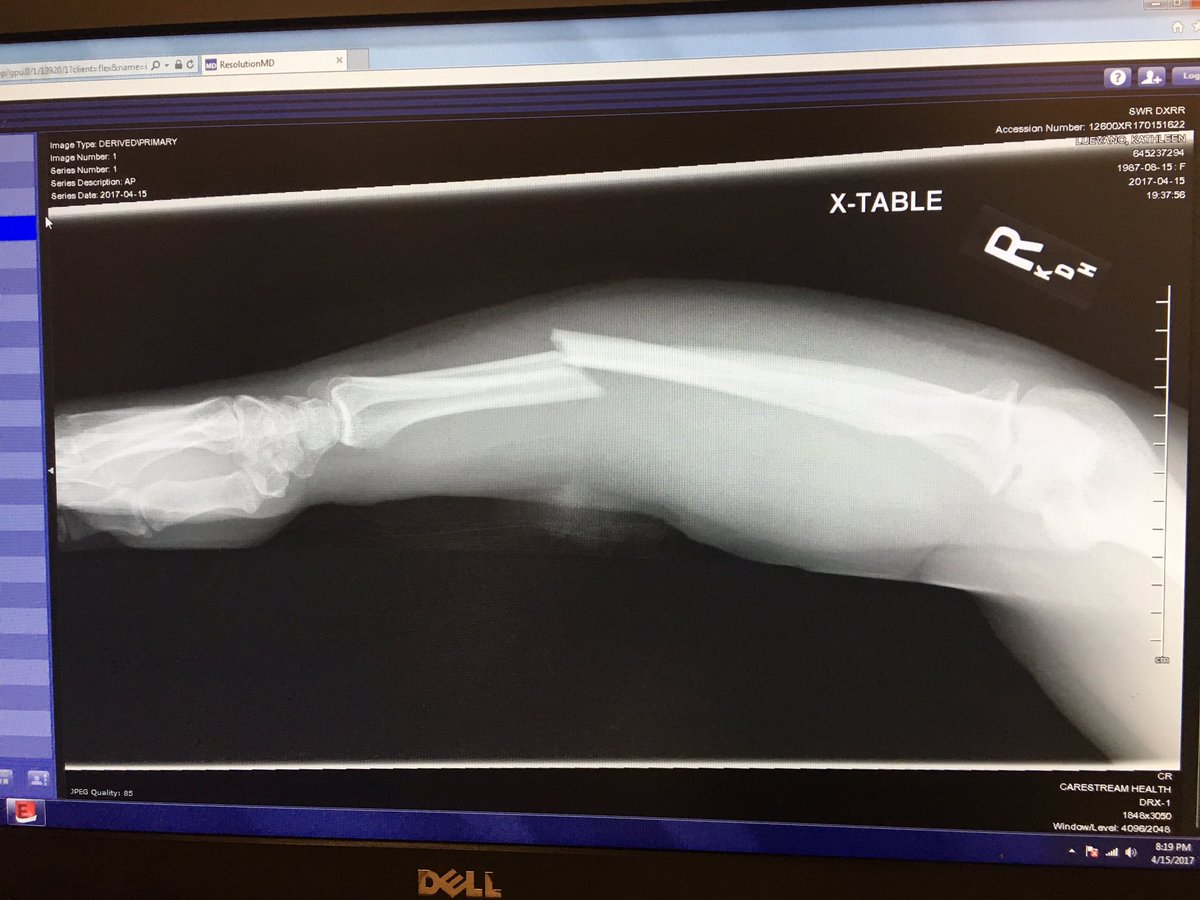

Fought a bear, broke both bones in my right arm, had surgery. The bear got it worse.pic.twitter.com/tACP2mTaTS